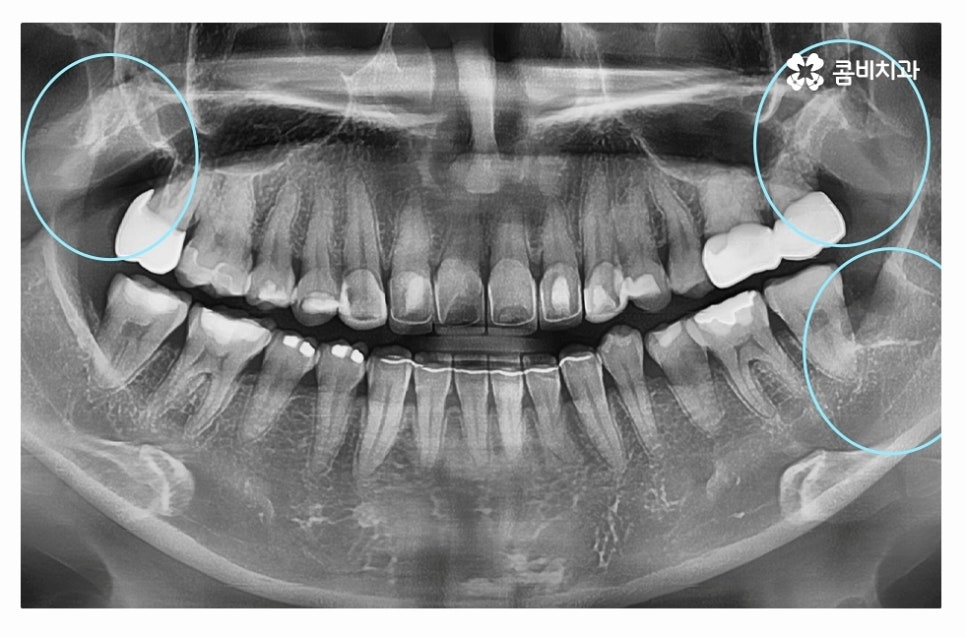

다음 사례를 살펴보면 위 사례와 마찬가지로 사랑니가 정상적으로

맹출 되어 있지 않고 어금니 뿌리 쪽으로 자라고 있는데요

위 환자분의 경우 사랑니와 어금니 사이에 충치가 발생하여

어금니 손상까지 (엑스레이상 좌측 위 사랑니) 유발된 사례라고 할 수 있어요.

사랑니의 경우 발치를 하면 되지만 어금니는 평생 지켜야 한다는 점에서

치아 수명이 줄어들게 되니 안타까운 상황이라고 할 수 있는데요.

사랑니로 인해 충치가 발생한 좌측 위 사랑니도 발치를 진행했지만

우측 사랑니도 위치가 좋지 않아서 누운사랑니발치 진행하였고

사랑니로 인해 충치가 발생된 어금니의 경우 크라운 치료를

해야 했던 만큼 사랑니는 주기적으로 검진이 필수라고 할 수 있어요.